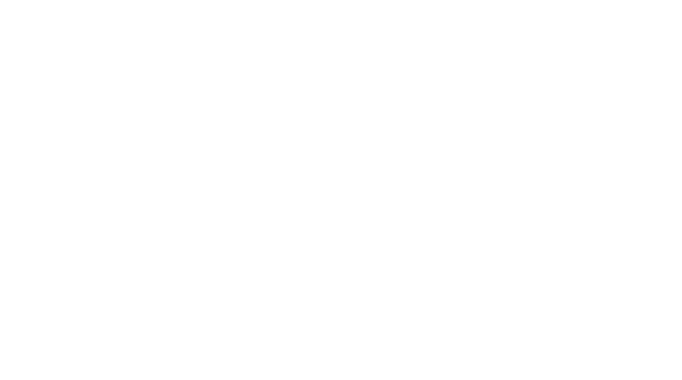

Clinical Images

Mitral and Tricuspid Regurgitation

Clinical Images

Mitral and Tricuspid Regurgitation